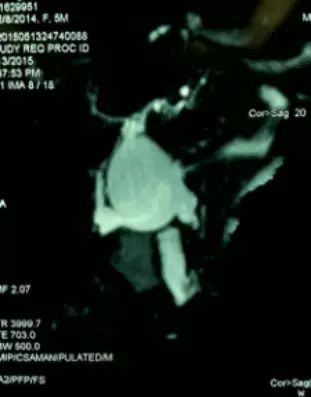

2.小儿外科创造性地利用术前MR 胆道三维重建与术中胆道造影相结合的方法,精准地判断胆总管囊肿的类型、胆总管末端与胰管的关系、肝管是否狭窄,从而在术中能精确地剥离胆总管、处理肝管狭窄。

患儿因“腹痛、皮肤黄染3天”以“胆总管囊肿、胆道梗阻并感染”入院。行腹部MR检查发现胆总管呈囊状扩张,入院后在B超引导下行胆管穿刺引流术,出院后恢复1个月后再次入院。经引流管行逆行胆道造影,显示胆总管呈囊状扩张,胆总管、胰管合流异常。